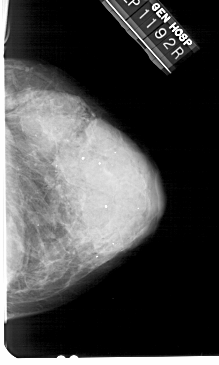

A_1936_1.RIGHT_MLO

RIGHT_CC LINES 5101 PIXELS_PER_LINE 3061 BITS_PER_PIXEL 12 RESOLUTION 43.5 NON_OVERLAY